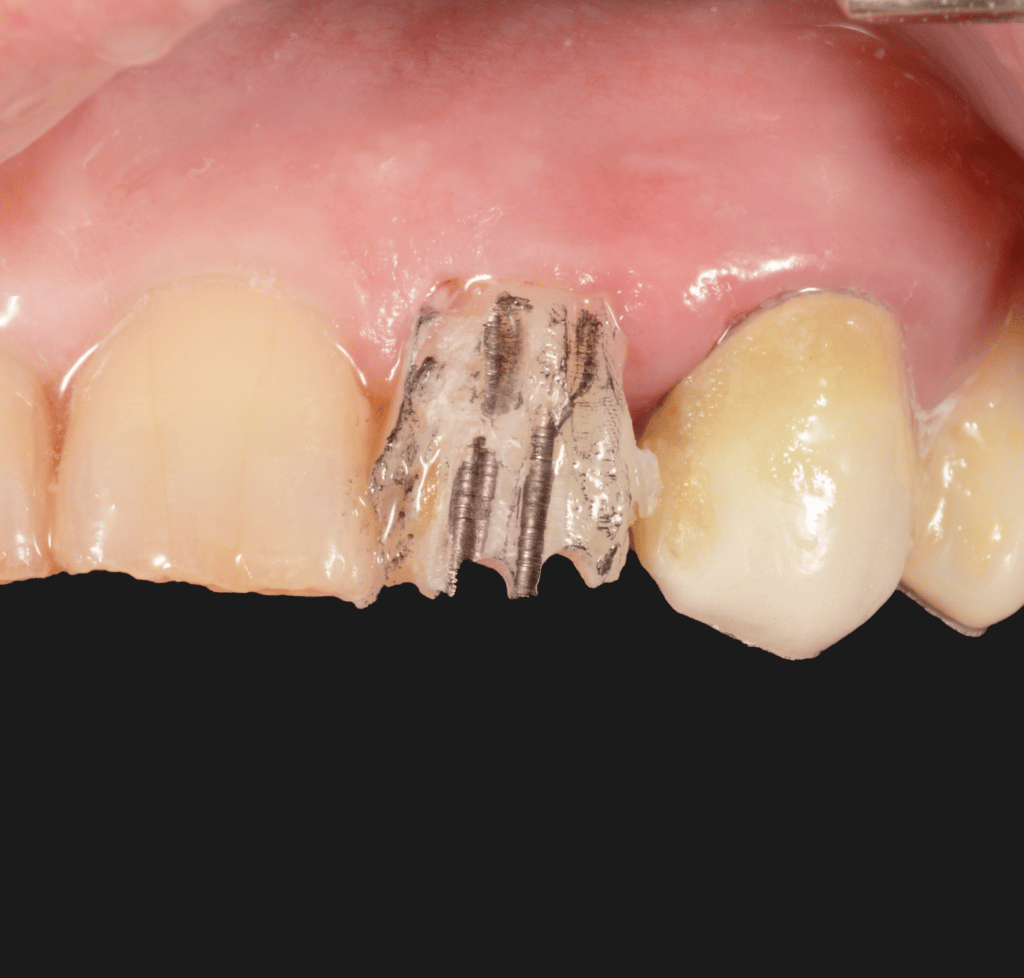

Patient came to our attention with a 2.2 fractured by trauma.

Clinical tests reveal: Vitality test: negative ; Percussion test: positive.

The endodontic treatment is performed with martensitic Niti instruments and obturated with single cone and Bioceramic sealer.

using Hawe steel matrix bands as scaffold, a build up is performed with flowable and packable composite. To increase the stabilization of the latter is used liquid rubberdam.

Isolated fractured tooth

fracture and martix scaffold

morphologic build up